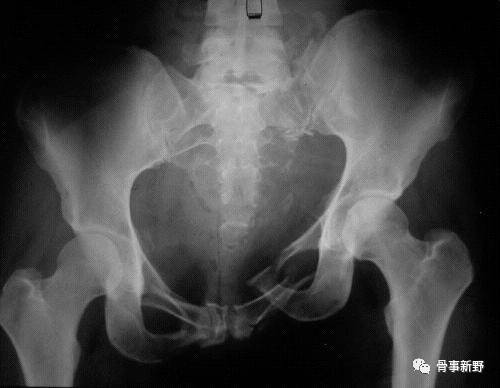

由Vidal J于1973年首次报道。骶髂螺钉是骶骨骨折及骨盆后环不稳使用最多的内固定方式之一,总体适用于无移位或移位较少的骶髂关节损伤、骶骨骨折。手术可在局麻下,经皮微创进行。

由Vidal J于1973年首次报道。骶髂螺钉是骶骨骨折及骨盆后环不稳使用最多的内固定方式之一,总体适用于无移位或移位较少的骶髂关节损伤、骶骨骨折(Mendel T, 2011)。手术可在局麻下,经皮微创进行。

(1)解剖变异识别:据文献报道,有高达40%的患者有骶骨解剖变异,术前影像资料仔细辨认,骨盆入口位可以很好显示畸形。